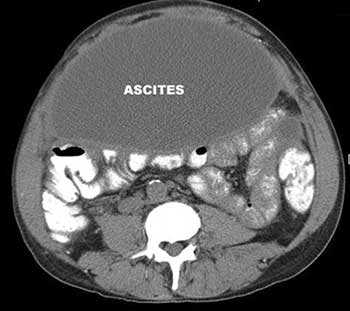

Асцит — патологическое состояние, при котором в брюшной полости скапливается жидкость. Причины его бывают различными. Чаще всего к асциту приводит цирроз печени. Так же он возникает как осложнение онкологических заболеваний, при этом ухудшается состояние больного, снижается эффективность лечения.

Если в брюшной полости скапливается небольшое количество жидкости (100-400 мл), симптомы отсутствуют. В таких случаях асцит обнаруживают зачастую случайно во время УЗИ или КТ органов брюшной полости.

- УЗИ, КТ и МРТ помогают диагностировать асцит и оценить количество жидкости в брюшной полости, состояние внутренних органов, обнаружить злокачественную опухоль, оценить количество, размеры, локализацию патологических очагов, степень прорастания опухоли в различные органы и ткани;